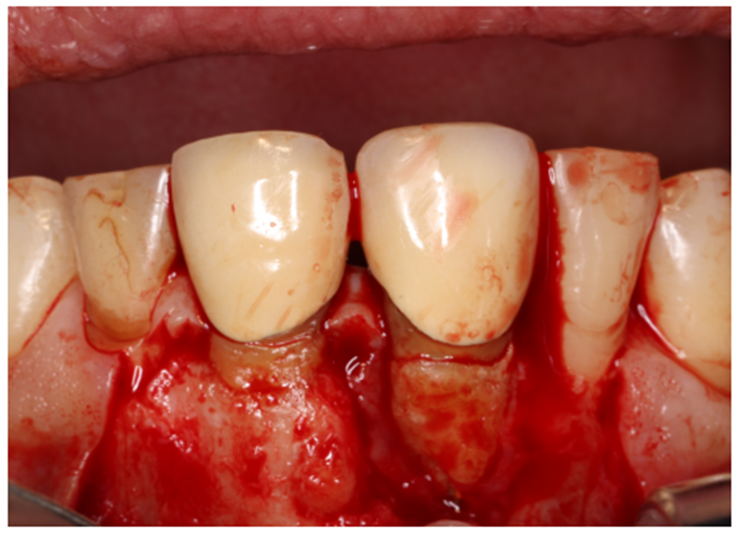

Paciente RV, do sexo masculino de 52 anos, compareceu a nossa clínica com queixa estética e funcional dos dentes incisivos centrais superiores. No exame clínico observou-se doença periodontal severa com presença de bolsa periodontal e perda óssea marginal maior do que 7 mm (Figura 1). Foi realizado em nossa escola (Beo – Ensino Odontológico Avançado) uma tomografia computadorizada para melhor planejamento cirúrgico do caso, onde confirmamos a necessidade de regeneração óssea guiada com membrana Cytoplast com reforço de titânio, devido à perda óssea vertical maior do que 7 mm (Figura 2). Após definição do planejamento cirúrgico, foi realizado a exodontia dos incisivos centrais superiores, limpeza cirúrgica da região e osteotomia periférica para melhor preparo do leito receptor do material de enxertia de lenta reabsorção Bio-Oss (Geistlich) e da membrana Cytoplast com reforço de titânio 30 mm X 40 mm (Figuras 3,4 e 5). Após estabilização da membrana, foi realizado a sutura com fio do tipo Cytoplast 3.0 mm devido a sua alta plasticidade, diminuindo o risco de deiscência de sutura (Figura 6).